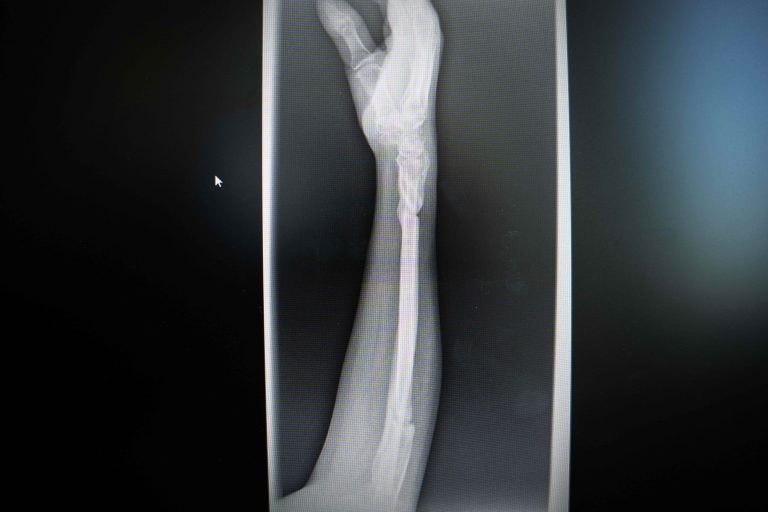

POS MB 708 12X-ray of Delay’s broken arm, survivor of extreme violencePOS MB 708 12$500

POS MB 708 13X-ray of Delay’s broken arm, survivor of extreme violence POS MB 708 13$500